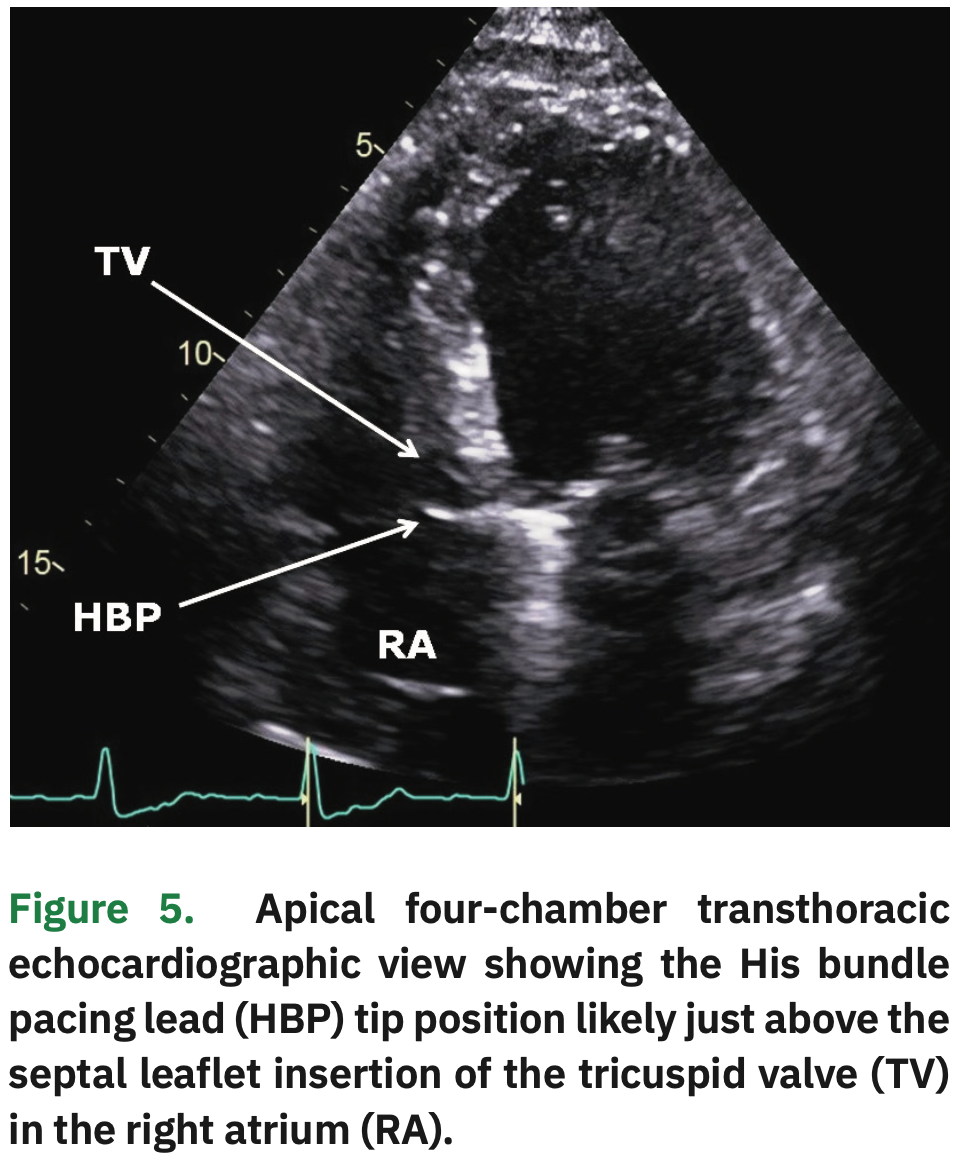

JCDD Free FullText Biventricular versus Conduction System Pacing Heart Node Ablation Web atrioventricular (av) node ablation uses heat energy, called radiofrequency energy, to destroy the area. Web what is an av node ablation? Web ablation is a procedure to treat atrial fibrillation. Heart ablation (also called cardiac ablation) describes a variety of procedures that. It uses small burns or freezes heart cells to cause some scarring on the. Web av node. Heart Node Ablation.

Atrioventricular Node Ablation Combined with His Bundle Pacing to Heart Node Ablation Heart ablation (also called cardiac ablation) describes a variety of procedures that. Web what is an av node ablation? Web ablation is a procedure to treat atrial fibrillation. The av node is a small area of tissue which sends an electrical heartbeat signal from your upper. Web av node ablation with pacemaker implantation has a very high success rate and. Heart Node Ablation.